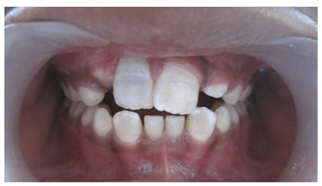

A 10year old boy reported to the department of Pedodontics with a chief complaint of missing upper front tooth and gave a history of fall from bike while 5 days back. They had been to pediatrician for the lacerated lip and got it sutured. Parents had kept the avulsed tooth in paper without knowledge of reimplantation of the same tooth. Patient had no relevant medical and family history. On examination swelling and suture was present on upper lip, lacerated gingiva with healing socket in 11 regions. 21 was intact, vital and non mobile. (Figure 1) (Figure 2) On examination of avulsed tooth 11, it was found to have open apex (Figure 3). On intraoral radiographic examination, no fracture was seen with alveolar bone (Figure 4). Thus avulsed tooth was cleaned and debrided with soft pumice prophylaxis, gentle scaling was done to remove ligament remnants. It was then placed in 1.23% sodium fluoride for 15minutes. Extraoral endodontic therapy was also done using retrograde filling of MTA (Figure 5). Local anesthesia was administered and socket was cleaned, curetted and irrigated to remove clot and debris and 11 was slowly reimplanted in socket. Orthodontic wire – composite splinting was done for 4weeks as the dry storage was more than 60minutes (Figure 6). Systemic antibiotics amoxicillin and doxycycline were prescribed for 5days. The patient was recalled after 1 month and splint was removed. No mobility was present. Again patient was recalled after 2months to check the condition (Figure 7). Again patient was recalled after 6months; tooth had slightly discolored but was not mobile and maintained the space (Figure 8). Patient was happy and contended with the reimplantation of his own tooth without disturbing his original look.

Figure 2 Intraoral pre-operative photograph.